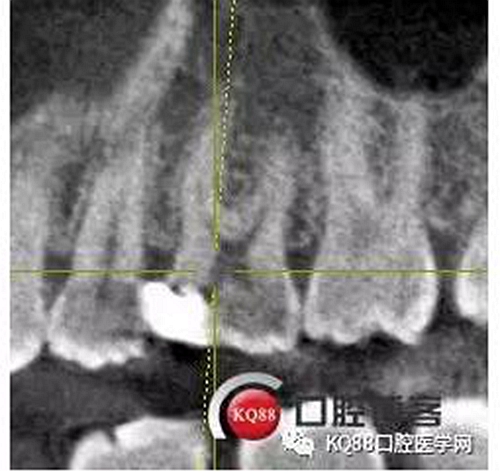

25遠(yuǎn)中鄰牙合面齲壞達(dá)髓腔,引起的牙髓炎,之后發(fā)展成為根尖炎的一個(gè)常見(jiàn)病例,上頜前磨牙,一看,心理都會(huì)覺(jué)得有啥啊,兩個(gè)根管,開(kāi)髓后,直接擴(kuò)了,不會(huì)有任何壓力,幸運(yùn)的是我們有CT,所以我就開(kāi)始都會(huì)定位下根管口,然后看到的事情告訴我其實(shí)上頜前磨牙不一定有我們想象的那么簡(jiǎn)單。

這兩張角度的截圖告訴我們這個(gè)牙齒一個(gè)典型的Y型根管,髓腔非常巨大,從根管口看,貌似一個(gè)根管口,但是根管銼下去以后,會(huì)兩個(gè)方向角度的分開(kāi)。因?yàn)槲覀儸F(xiàn)在都是常規(guī)的機(jī)擴(kuò)與熱牙膠充填,建立直線根管口的暴露就變得非常重要,必須直線視野下操作,機(jī)擴(kuò)才不會(huì)發(fā)生扭曲折斷。目前市面上的根管銼有很多,M3,S3等,而此次我使用的是歐羅德卡PLEX軟銼,因?yàn)槭强谇?8贈(zèng)送我的,所以我就先嘗試的使用了一下,我不會(huì)單方面的去評(píng)價(jià)比別的好,我覺(jué)得預(yù)備方法對(duì)了,都會(huì)很不錯(cuò),只能說(shuō)一句這個(gè)用起來(lái)軟銼對(duì)后牙的預(yù)備確實(shí)不錯(cuò)。根管預(yù)備,常規(guī)我都會(huì)先C銼疏通,如果直接15號(hào)很有可能會(huì)在根尖方形成臺(tái)階,以后就很難再下去了,當(dāng)C銼到達(dá)根尖孔后,予以初步測(cè)量長(zhǎng)度,在用疏通機(jī)擴(kuò)針通入,然后一步步規(guī)范化開(kāi)始,逐級(jí)預(yù)備,一個(gè)簡(jiǎn)單的經(jīng)驗(yàn),如果當(dāng)使用的銼不容易到達(dá)根尖時(shí),不要著急,用上一號(hào),繼續(xù),再回來(lái),就可以了,不然形成臺(tái)階,就很難操作了,常有人會(huì)覺(jué)得擴(kuò)根時(shí),突然發(fā)現(xiàn),下不去了,排除斷針的可能性的話,臺(tái)階是最重要的,擴(kuò)根時(shí),1%次氯酸鈉變沖洗,變預(yù)備,防止碎屑推出根尖孔,我沖洗常使用1%次氯酸鈉與蒸餾水,再充填前,會(huì)使用EDTA沖洗液去除根管壁油污。